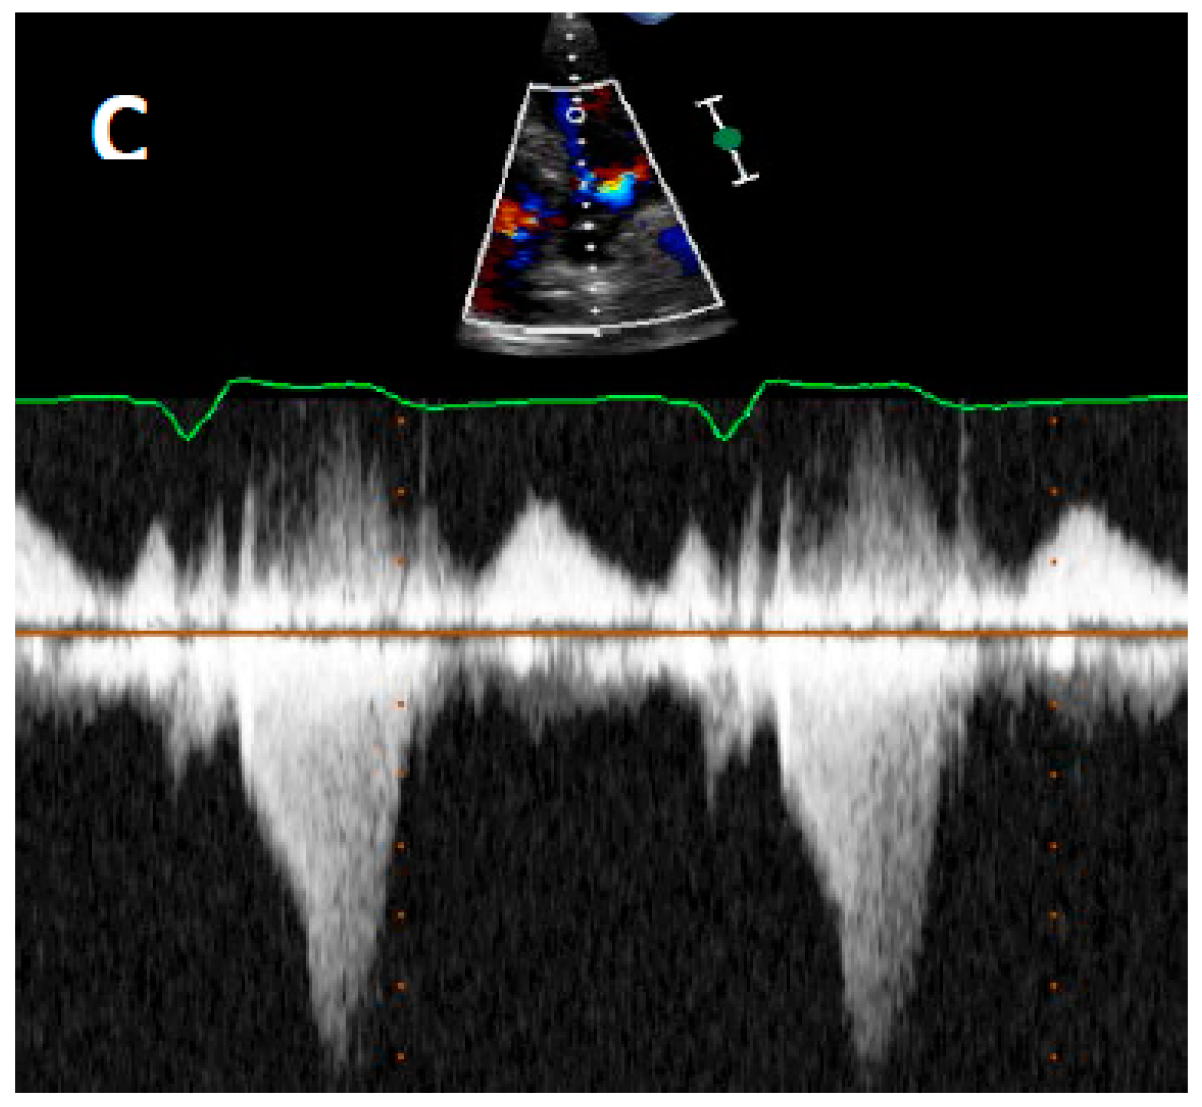

4.2. Echocardiography

5. Current Diagnostic Techniques